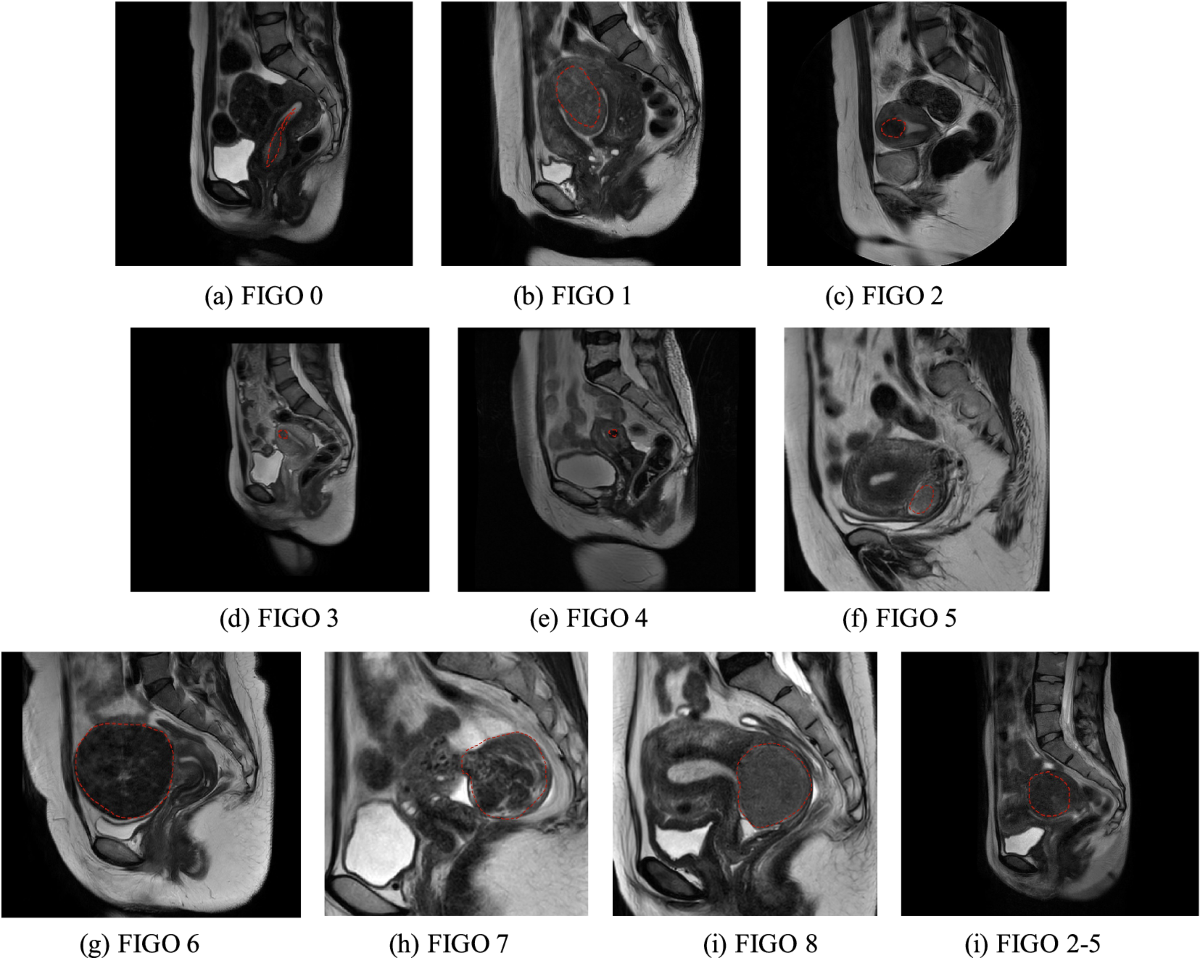

The challenge of FIGO type 3 leiomyomas and infertility: Exploring therapeutic alternatives amidst limited scientific certainties - Favilli - 2024 - International Journal of Gynecology \u0026 Obstetrics - Wiley Online Library

Uterine fibroid : FIGO classification and some examples How to comment on uterine fibroid 1- site ( anterior , posterior wall , fundus) / upper or lower / right or left 2-

image size: 2008x2188